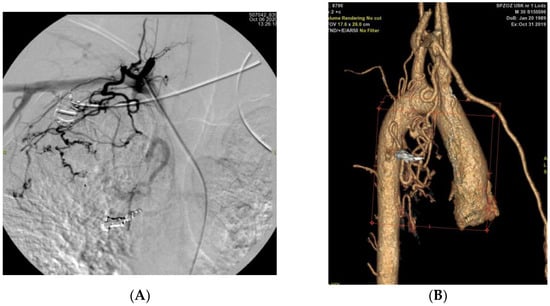

| Case Number | Computed Tomography Angiography Findings | Culprit Vessel Identified on Digital Subtraction Angiography | Match |

|---|---|---|---|

| P01 | Dilated, tortuous R BA | R BA | Yes |

| Dilated, tortuous R BA (up to 3 mm) Bilateral bronchiectasis (RUL, LUL, RML dominant) Mild consolidations | R BA | Yes | |

| Dilated, tortuous R BA (up to 2.9 mm) Bilateral bronchiectasis (RUL, LUL, RML dominant) Focal consolidation in apical segments (LUL) | L subclavian a. | Yes | |

| P03 | LIMA dilated to 3.1 mm; L BA to 3.3 mm; L inferior phrenic a. to 3.1 mm Post-inflammatory changes bilaterally Fibrotic transformation of LL | L Th12 aortic branch (phrenic a.) | Yes |

| Persistent vascular abnormalities, comparable to prior CTA | R subclavian a. | Yes | |